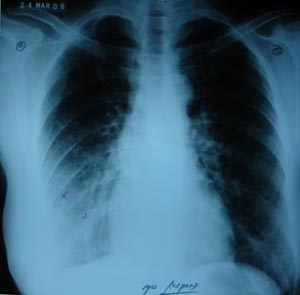

Right lower zone opacity

Multiple fibrotic bands in right lower zone & fine obliteration of right costophrenic angle is suggestive of thickened pleura, as a sequele of resolveing pleural effusion.